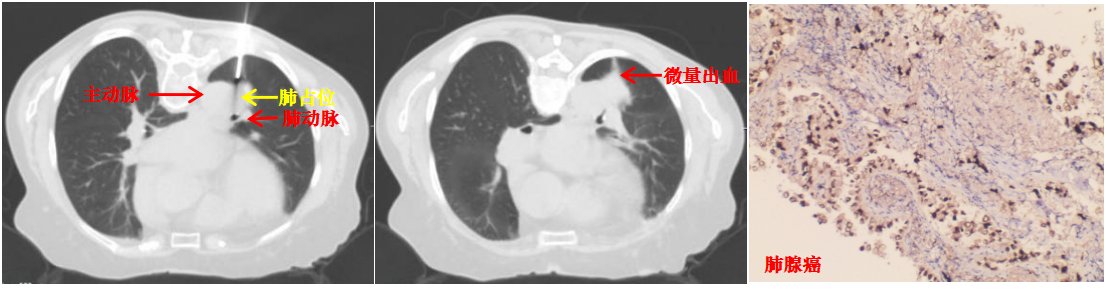

本病例患者肺结节穿刺中(左图)、穿刺后(中图)和病理诊断(右图)

面对诊疗压力与家属的殷切期盼,陆霓虹主任带领呼吸介入团队开展周密术前讨论,反复对患者CT影像进行三维重建和多角度研判,精密测算进针点、角度及深度。同时,针对术中可能出现的咯血、气胸、空气栓塞等并发症,制定了严密的“阶梯式”应急方案。主管医师吴文娟博士及赵思蓉医师用通俗易懂的方式讲解穿刺方案,最终打消了家属的不安与疑虑。

取得患者及家属同意后,陆霓虹主任带领介入团队医生杨嫄、贺晓洁,护士杨红艳、王丽,在CT引导下实施穿刺活检。影像监控下,针尖精准抵达病灶核心,实时测量显示针尖距离主动脉仅4mm,团队迅速完成切割取材,仅出现极少量创面出血,对症处理后患者安返病房,无出血、气胸等并发症。

术后病理确诊为肺腺癌,为患者后续治疗提供了决定性依据。此次技术突破,是科室在高危肺结节诊疗领域的又一跨越。未来,昆医大附二院呼吸与危重症医学科介入团队将持续精进技术、优化诊疗流程,为更多高危肺结节患者提供精准、安全的微创诊疗服务。